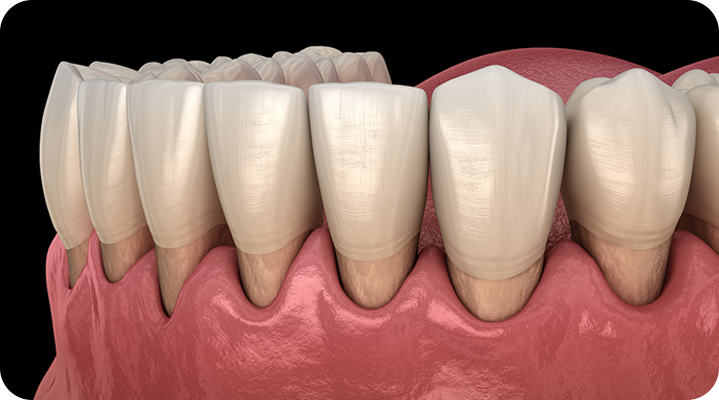

“자연치아 살리기 최우선 진료”

서울하나치과는 자연치아의 가치를 알기에 언제나 자연치아를 우선적으로 보존하기 위해 노력합니다.

건강한 치아는 건강한 잇몸이 있기에 존재합니다. 성인 대부분이 잇몸 질환을 모르고 방치하고 있습니다. 잇몸질환, 더 이상 방치하지 말고 관리를 통해 개선해보세요!

PERIODONTAL DISEASE

치주낭 길이 3mm 이하

치주낭 길이 3~5mm 이하

치주낭 길이 5~7mm 이하

치주낭 길이 7mm 이상